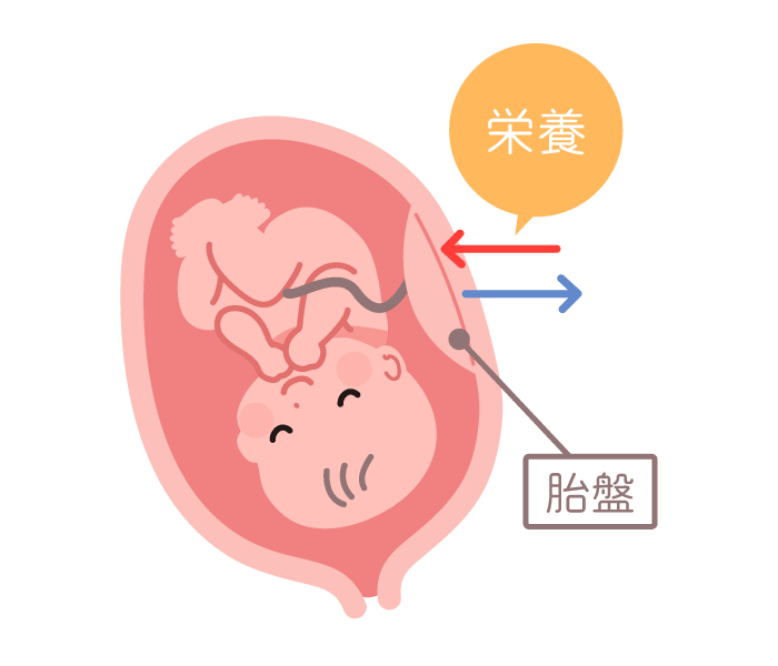

おなかの中で成⻑する赤ちゃんはお母さんと胎盤で血管を通してつながっていて、その血管から赤ちゃんに栄養が送られています。そのため、赤ちゃんのDNAの一部がこの血管を通じてお母さんの体内へ移動して、お母さんの血液中に少量存在するのです。これがお母さんの血液を検査することで赤ちゃんの情報がわかる理由です。